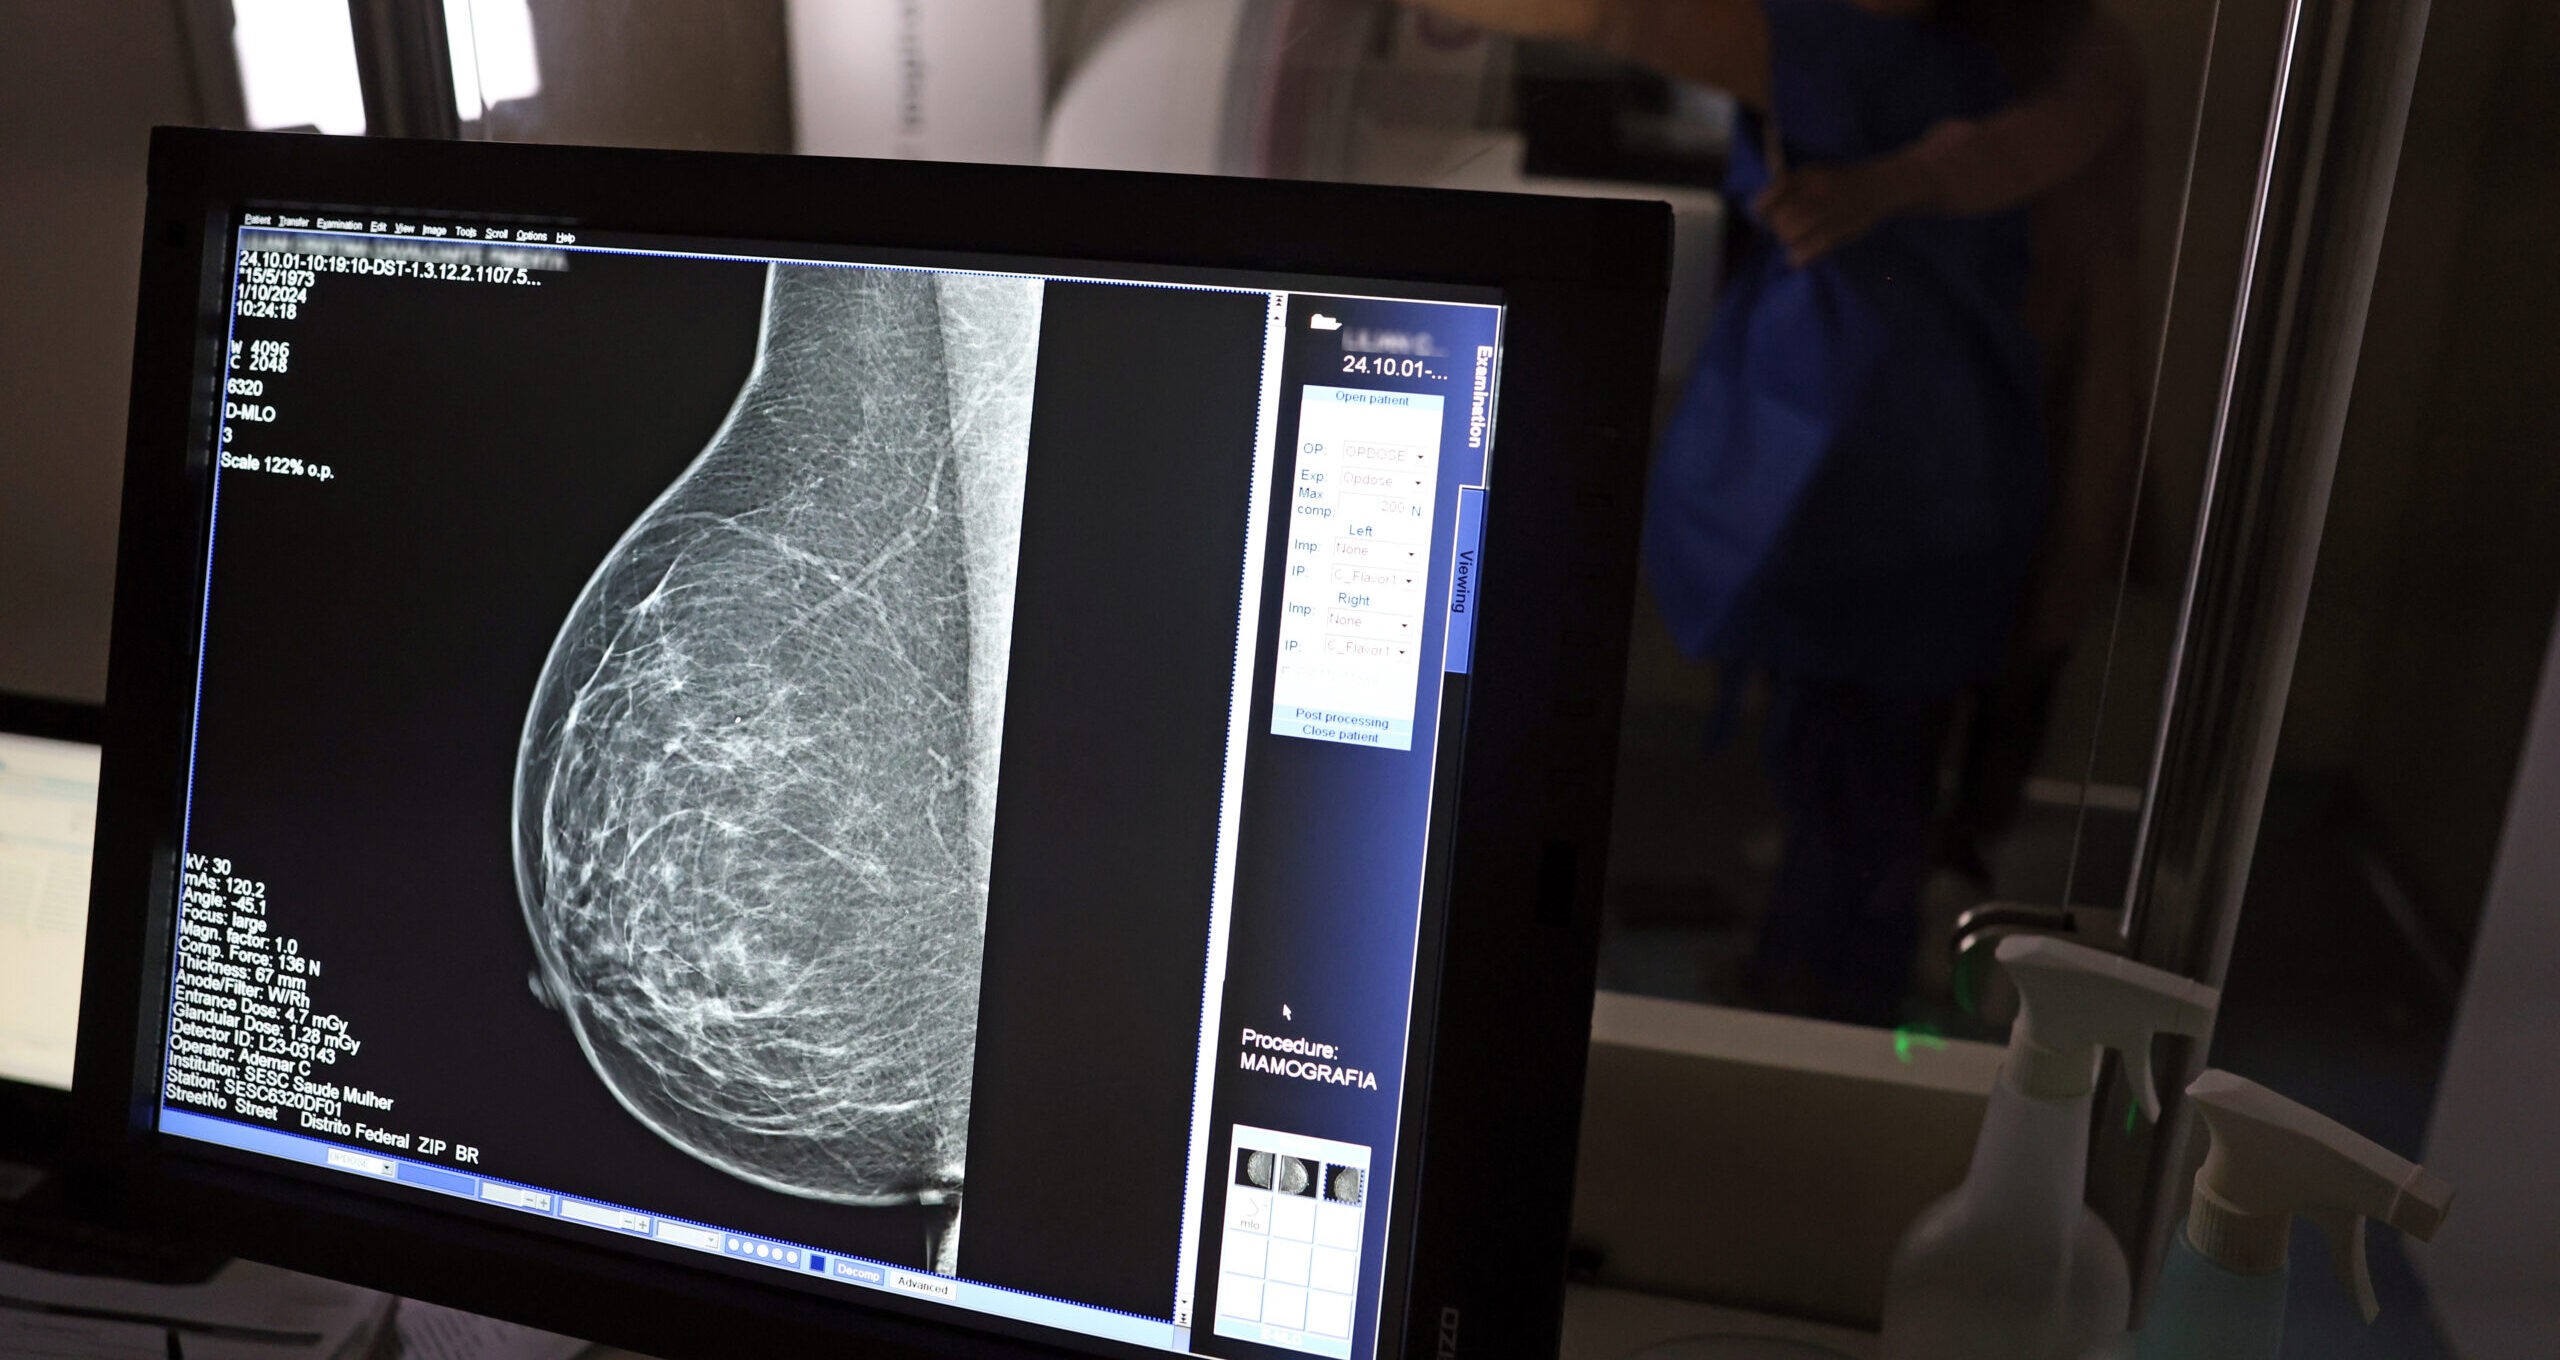

A inteligência artificial (IA) mostra-se promissora na identificação do risco de doenças cardiovasculares em mulheres, utilizando como base as análises de mamografias. Este achado faz parte de um estudo recente promovido pela Sociedade Europeia de Cardiologia, que foi publicado na respeitada revista científica “European Heart Journal”.

Os pesquisadores descobriram que a IA é capaz de detectar o acúmulo de depósitos de cálcio nas artérias mamárias através de exames de raio-X, que são amplamente utilizados para o rastreamento de câncer de mama. É importante destacar que a calcificação arterial observada nas mamografias não está relacionada a tumores, mas pesquisas anteriores já associaram a presença de calcificações a fatores de risco cardiovascular e ao potencial desenvolvimento de doenças cardíacas no futuro.

O estudo contou com a participação de mais de 123 mil mulheres que se submeteram a rastreamentos mamográficos e que não apresentavam doenças cardiovasculares previamente diagnosticadas. A IA foi utilizada para avaliar a quantidade de depósitos de cálcio nas artérias do tecido mamário, classificando a calcificação em quatro categorias: grande, moderada, leve ou ausente.